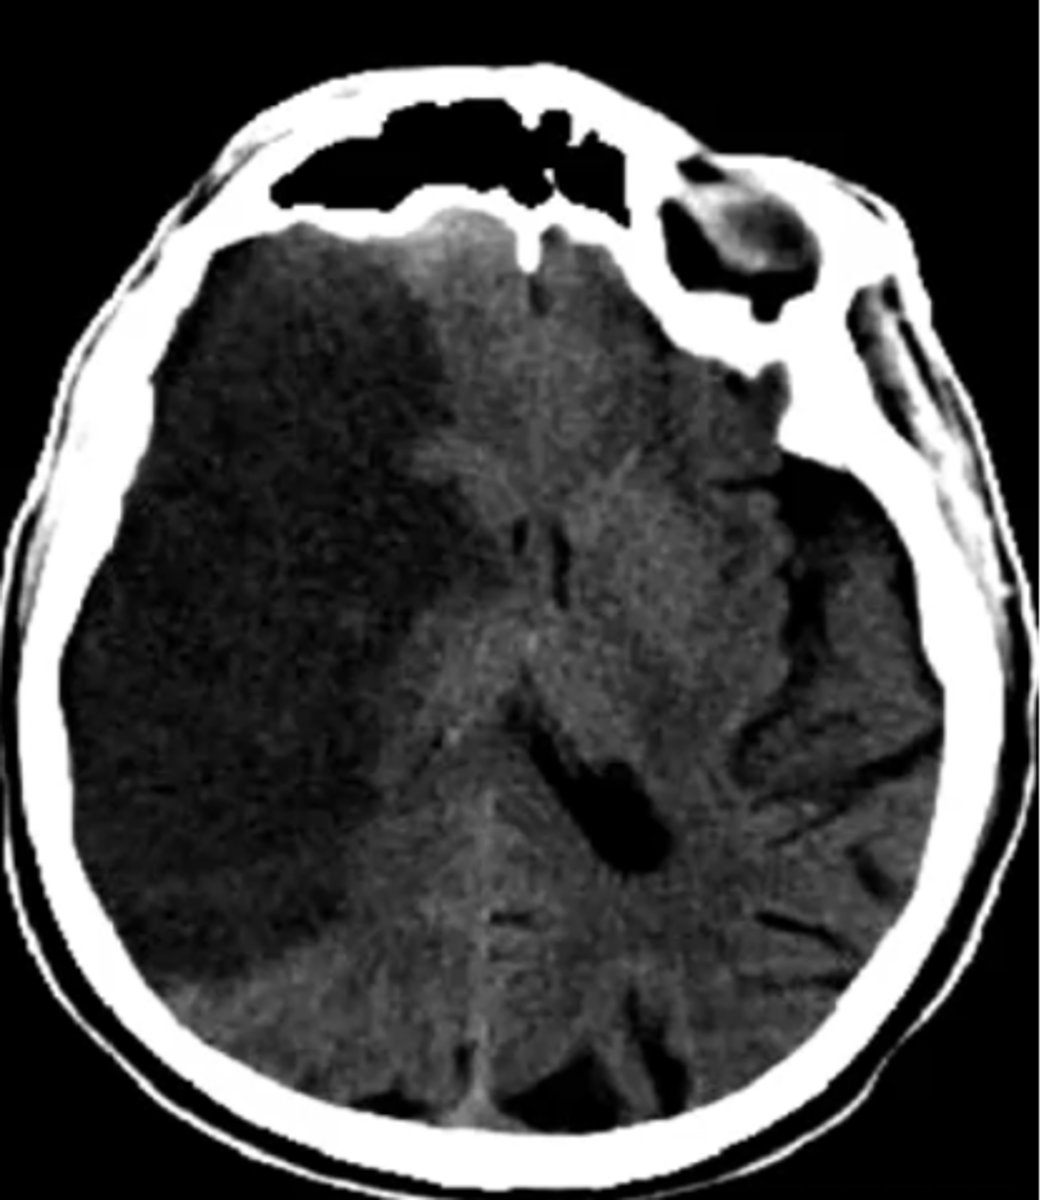

Middle cerebral artery (MCA)

What vascular area is affected by this stroke?